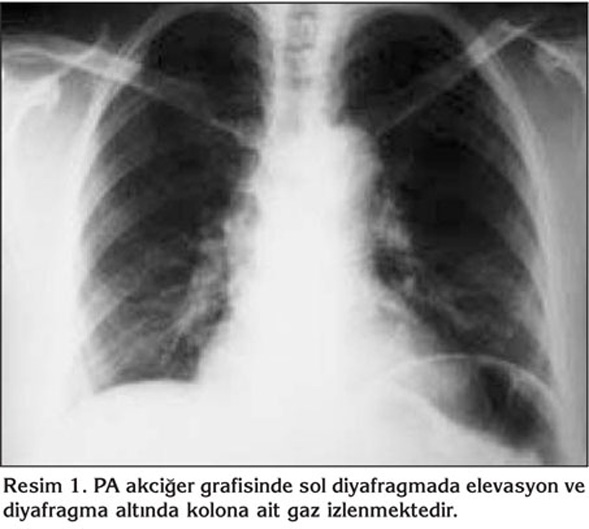

Elli sekiz ya??nda kad?n hasta, tekrarlayan ?ks?r?k ?ikayetiyle hastanemize ba?vurdu. Hasta ev han?m? idi ve sigara kullanm?yordu. ?yk?s?nde uzun s?redir nonprod?ktif ?ks?r?k ?ikayetine ek olarak s?k bo?az temizleme hissi ve bo?az a?r?s? mevcuttu. ?la? kullan?m ?yk?s? yoktu. Fizik muayenesi ve solunum fonksiyon testleri normal s?n?rlarda idi. Radyolojik tetkiklerinde; PA akci?er grafisi normal s?n?rlarda olan hastan?n waters grafisinde sa? maksiller sin?zit ile uyumlu bulgular? ve kontrastl? toraks bilgisayarl? tomografisi (BT)'nde diyafragma ?zerinde, sa? atriyum posterior kom?ulu?unda, ?VK'da anevrizmal geni?leme saptand? (Resim 1, 2). Yap?lan venografi incelemesiyle torasik ?VK segmentinde sakk?ler anevrizmal dilatasyon varl??? teyit edildi (Resim 3).